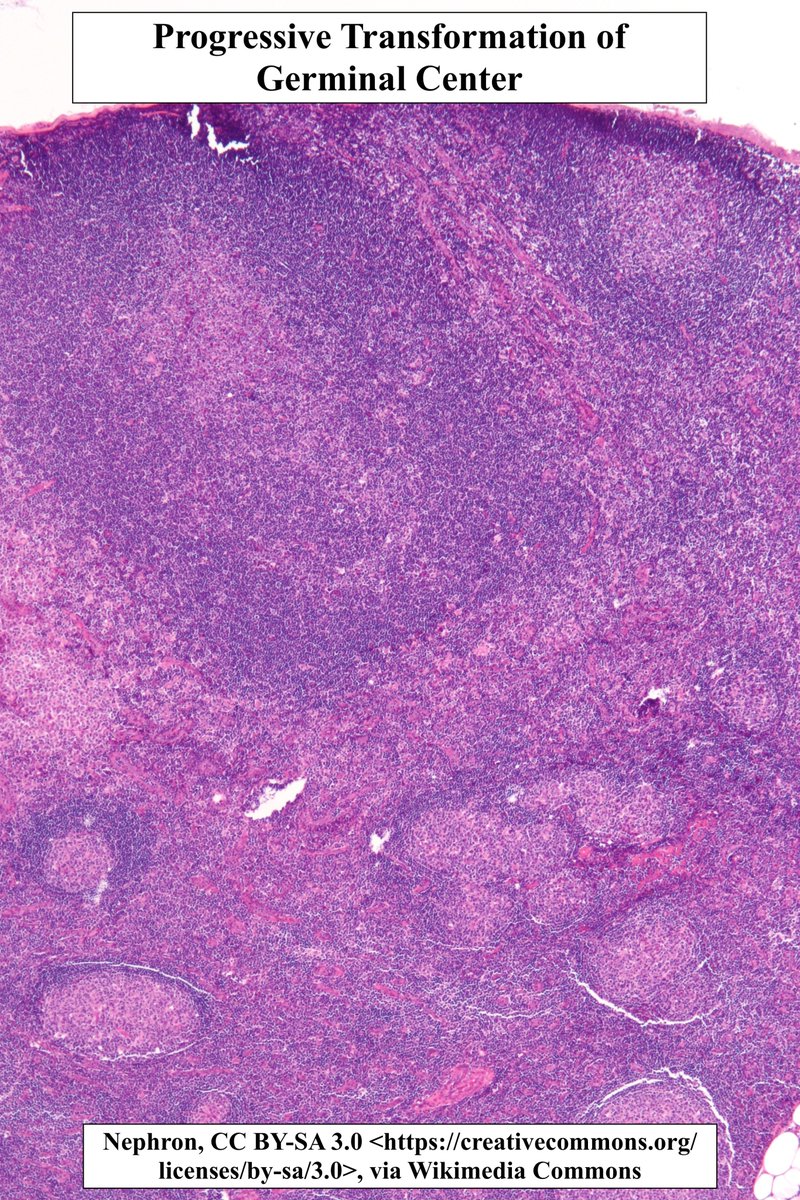

Progressive Transformation of Germinal Centers (PTGC) •Characterized by chronic lymphadenopathy w wide age distribution •🔬Expansile follicles w mantle zone expanding into+disrupting germinal center •Benign but may be ass w/ NLP Hodgkin's Lymphoma #pathagonia #heme #pathx

Progressive Transformation of Germinal Centers (PTGC)

•Characterized by chronic lymphadenopathy w wide age distribution

•🔬Expansile follicles w mantle zone expanding into+disrupting germinal center

•Benign but may be ass w/ NLP Hodgkin's Lymphoma

#pathagonia  #heme #pathx